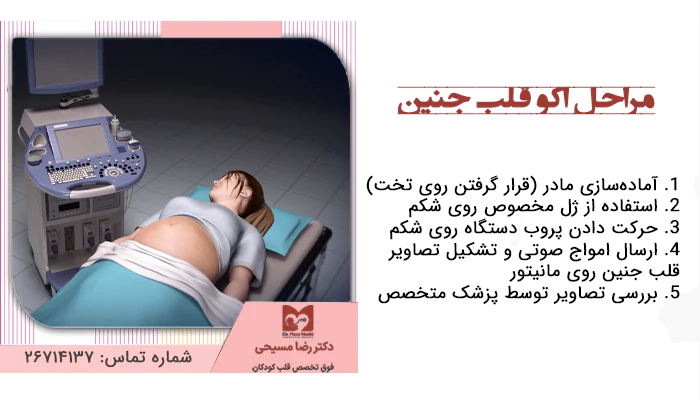

روش انجام اکو قلب جنین از نظر ظاهر بسیار شبیه سونوگرافی است. شما روی تخت دراز میکشید، ژل مخصوصی روی شکمتان قرار داده میشود و پروب دستگاه روی آن حرکت میکند تا تصاویر واضحی از قلب جنین بهدست بیاید. تفاوت این آزمایش با سونوگرافی در دقت و تخصصی بودن آن است. بهترین دکتر اکو قلب جنین در طول انجام اکو فقط روی قلب جنین تمرکز میکند و کوچکترین جزئیات مانند دریچهها، دیوارهها و حفرههای قلب را با دقت بررسی میکند.

آمادهسازی مادر (قرار گرفتن روی تخت)

وقتی وارد اتاق میشوید، ابتدا از شما خواسته میشود روی تخت مخصوص معاینه دراز بکشید. معمولاً به پشت قرار میگیرید، اما اگر در این وضعیت احساس راحتی نداشتید، میتوانید کمی به پهلو بچرخید. این کار باعث میشود پزشک بتواند راحتتر پروب دستگاه را روی شکمتان حرکت دهد.

استفاده از ژل مخصوص روی شکم

پس از آمادهسازی، پزشک مقداری ژل شفاف و خنک روی سطح شکم شما میریزد. شاید در همان لحظه احساس کنید ژل کمی سرد است، اما این حس موقتی است و خیلی زود به آن عادت خواهید کرد.

این ژل نقش مهمی در کیفیت تصاویر دارد و وجود آن کمک میکند امواج صوتی بدون هیچ مانعی وارد بدن شما شوند و تصویر قلب جنین بهوضوح روی مانیتور تشکیل شود. بدون استفاده از ژل، کیفیت تصاویر پایین میآید و پزشک نمیتواند بررسی دقیقی انجام دهد.

حرکت دادن پروب دستگاه روی شکم

بعد از زدن ژل، پزشک پروب دستگاه را که وسیلهای کوچک است و امواج صوتی را ارسال و دریافت میکند، روی شکم شما قرار میدهد. سپس آن را بهآرامی در بخشهای مختلف شکم شما حرکت میدهد تا تمام قسمتهای قلب جنین در تصویر مشخص شود.

ارسال امواج صوتی و تشکیل تصاویر قلب جنین روی مانیتور

پروب دستگاه، امواج صوتی با فرکانس بالا را به سمت بدن شما میفرستد. این امواج پس از برخورد با قلب جنین بازتاب پیدا میکنند و دستگاه آنها را به تصویر تبدیل میکند. نتیجه این بازتابها بهصورت زنده روی مانیتور ظاهر میشود.

بررسی دقیق تصاویر توسط پزشک متخصص

وقتی تصاویر روی مانیتور تشکیل شد، بهترین فوق تخصص قلب جنین آنها را با دقت تحلیل میکند. او بررسی میکند که حفرهها و دریچههای قلب جنین شما شکل طبیعی داشته باشند و حرکات قلب نیز بهطور منظم انجام شود.